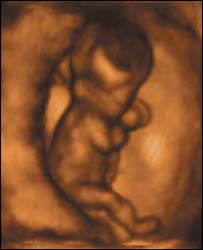

बच्चा 12वें हफ़्ते में अंगड़ाई लेने लगता है

भ्रूण

बारहवें सप्ताह में बच्चा गर्भाशय में 'चलने' लगता है

नए अल्ट्रॉसाउंड स्कैन ने जो तस्वीरें ली हैं उसमें 12 सप्ताह के भ्रूण को गर्भाशय में 'चलते' हुए देखा जा सकता है.

इतना ही नहीं नए स्कैन से यह भी देखा जा सकता है कि माँ के पेट में बच्चा किस तरह जम्हाई लेता है और किस तरह अपनी आँखें मलता है.

नई मशीन गर्भस्थ शिशु की हलचलों की तस्वीरें लेता है

- 12 सप्ताह का भ्रूण अंगड़ाई लेता है और हाथ पैर चलाने लगता है, हालांकि तब तक माँ को बच्चे की गतिविधियों का पता नहीं चलता है.

- 18 सप्ताह का भ्रूण अपनी आँखें खोलने लगता है, अब तक डॉक्टर मानते थे कि भ्रूण जब तक 26 सप्ताह का नहीं हो जाता वह अपनी आँखें नहीं खोलता.

-26 सप्ताह का बच्चा किसी बच्चे की ही तरह हरकतें करने लगता है, मसलन वह मुस्कुराता है, रोता है, हिचकियाँ लेता है, खुजलाता है और अंगूठा चूसता है.